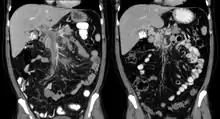

| Portal vein thrombosis seen with computed tomography. | |

The diagnosis of portal vein thrombosis is usually made with imaging confirming a clot in the portal vein; ultrasound is the least invasive method and the addition of Doppler technique shows a filling defect in blood flow. PVT may be classified as either occlusive or nonocclusive based on evidence of blood flow around the clot.[5] An alternative characterization based on site can be made: Type 1 is limited to the main portal vein, Type 2 involves only a portal vein branch (2a, or 2b if both branches are affected), and Type 3 if clot is found throughout both areas.[8] Determination of condition severity may be derived via computed tomography (CT) with contrast, magnetic resonance imaging (MRI), or MR angiography (MRA). Those with chronic PVT may undergo upper endoscopy (esophagogastroduodenoscopy, EGD) to evaluate the presence of concurrent dilated veins (varices) in the stomach or esophagus.[3] Other than perhaps slightly elevated transaminases, laboratory tests to evaluate liver function are typically normal.[1] D-dimer levels in the blood may be elevated as a result of fibrin breakdown.